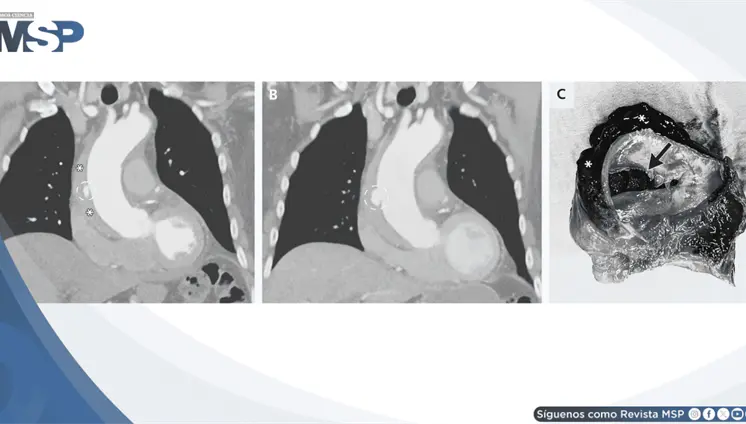

El estudio histológico confirmó un adenocarcinoma mucinoso de células en anillo de sello de vejiga con invasión muscular y diseminación metastásica pulmonar y ósea.

La pseudomelanosis vesical es una entidad extremadamente infrecuente, caracterizada por el depósito de pigmento de melanina en el urotelio y macrófagos de la lámina propia.